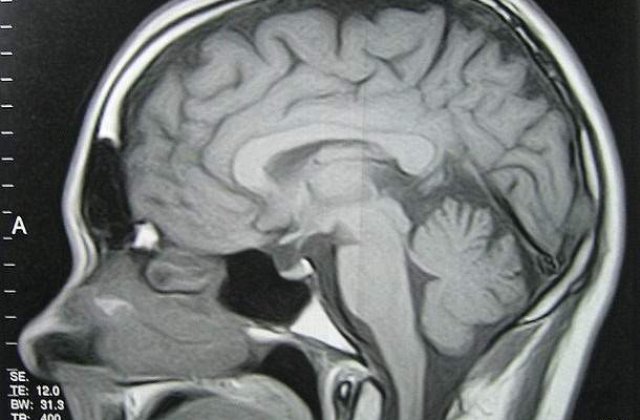

Dupa o lupta care a insemnat operatii multiple si multi bani cheltuiti, fiul sau, Denis, diagnosticat cu tumoare la creier, a reusit sa invinga cancerul, insa cheltuielile care au urmat au adus, din nou, familia Pascovici intr-o situatie dificila.

Fiul sau ia cate 7-8 pastile pe zi, tratamentul costand peste o mie de euro pe luna.

"Are acasa un frigider plin cu medicamente, ia cate sapte - opt pe zi. Ii e greata si, ca sa nu le simta gustul, maica-sa le trage printr-o seringa, le pune in suc si-i da sa bea. Medicamentele le luam din Franta, in Romania nu se gasesc toate si-n plus sunt foarte scumpe, iar tratamentul lunar costa peste 1.000 de euro", a spus fostul dinamovist.